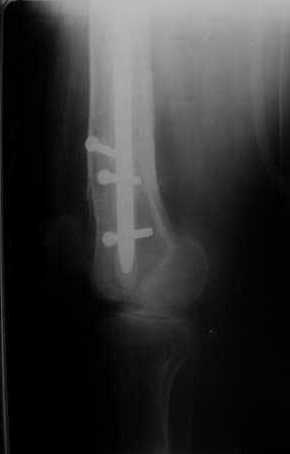

Мы демонтировали спице-стержневой аппарат, рассверлили костно-мозговой канал (до 14 мм), установили в канал спейсер с антибиотиком и произвели его блокирование четырьмя винтами ( рис. 1, 2, 3, 4).

В качестве армирующего элемента для спейсера мы использовали титановый неканюлированный штифт типа UFN (диаметр 9 мм, длина 400 мм). Проксимальную широкую часть штифта костным цементом не покрывали (рис. 5).

Дистальные блокирующие отверстия в цементе рассверлили после его застывания под ЭОП'ом. В проксимальном отломке использовали винт-полер (так как штифт проходил очень близко к переднему кортикальному слою).

В остальном, операция прошла без технических трудностей. Александр Николаевич, спасибо за ваши прекрасные развертки. Так не хочется отдавать их Вам обратно! Завтра пациент выписывается. Температура тела и анализы у него нормальные. Бедро мягкое, отечность тканей значительно уменьшилась. Послеоперационные раны зажили первичным натяжением. Укорочение конечности составляет 1,5 см (по ощущениям больного, это оптимальная длина ноги для него, так как у него анкилоз коленного сустава и голеностопного сустава в положении подошвенного сгибания). Пациент ходит с дозированной нагрузкой на конечность (10% от веса тела). Свищ на передне-наружной поверхности средней трети бедра, который открылся за неделю до последней операции рядом со стержнем аппарата, закрылся 5 дней назад (рис. 6,7, 8).